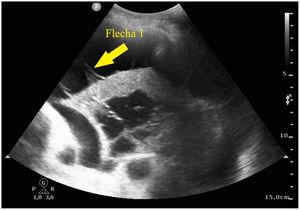

Ecografía pulmonar: absceso pulmonar secundario a neumonía necrotizante

Luis Javier Pérez Bazaga, Carlos Ávila Sansegundo, María Ángeles Santiago Triviño

Med Intensiva. 2024;48:244-5

Acceso a texto completo